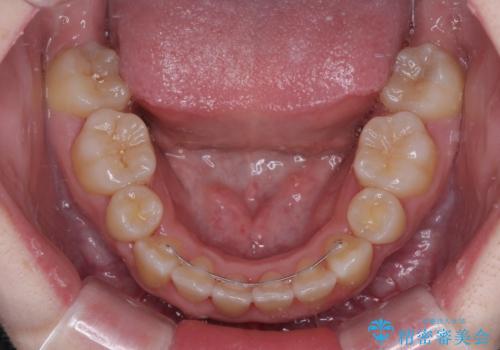

舌の突出癖を改善するためのトレーニングをしっかりと行っていただいたことで、比較的スムーズに治療を進めることができました。

口元の突出感もしっかりと改善することができました。